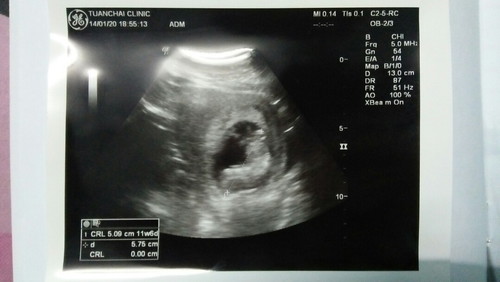

ฝากเรียบร้อย ลูก11w6d

ขอให้หนูแข็งแรงนะลูก ชายหรือหญิง พ่อก็รักหนูนะ